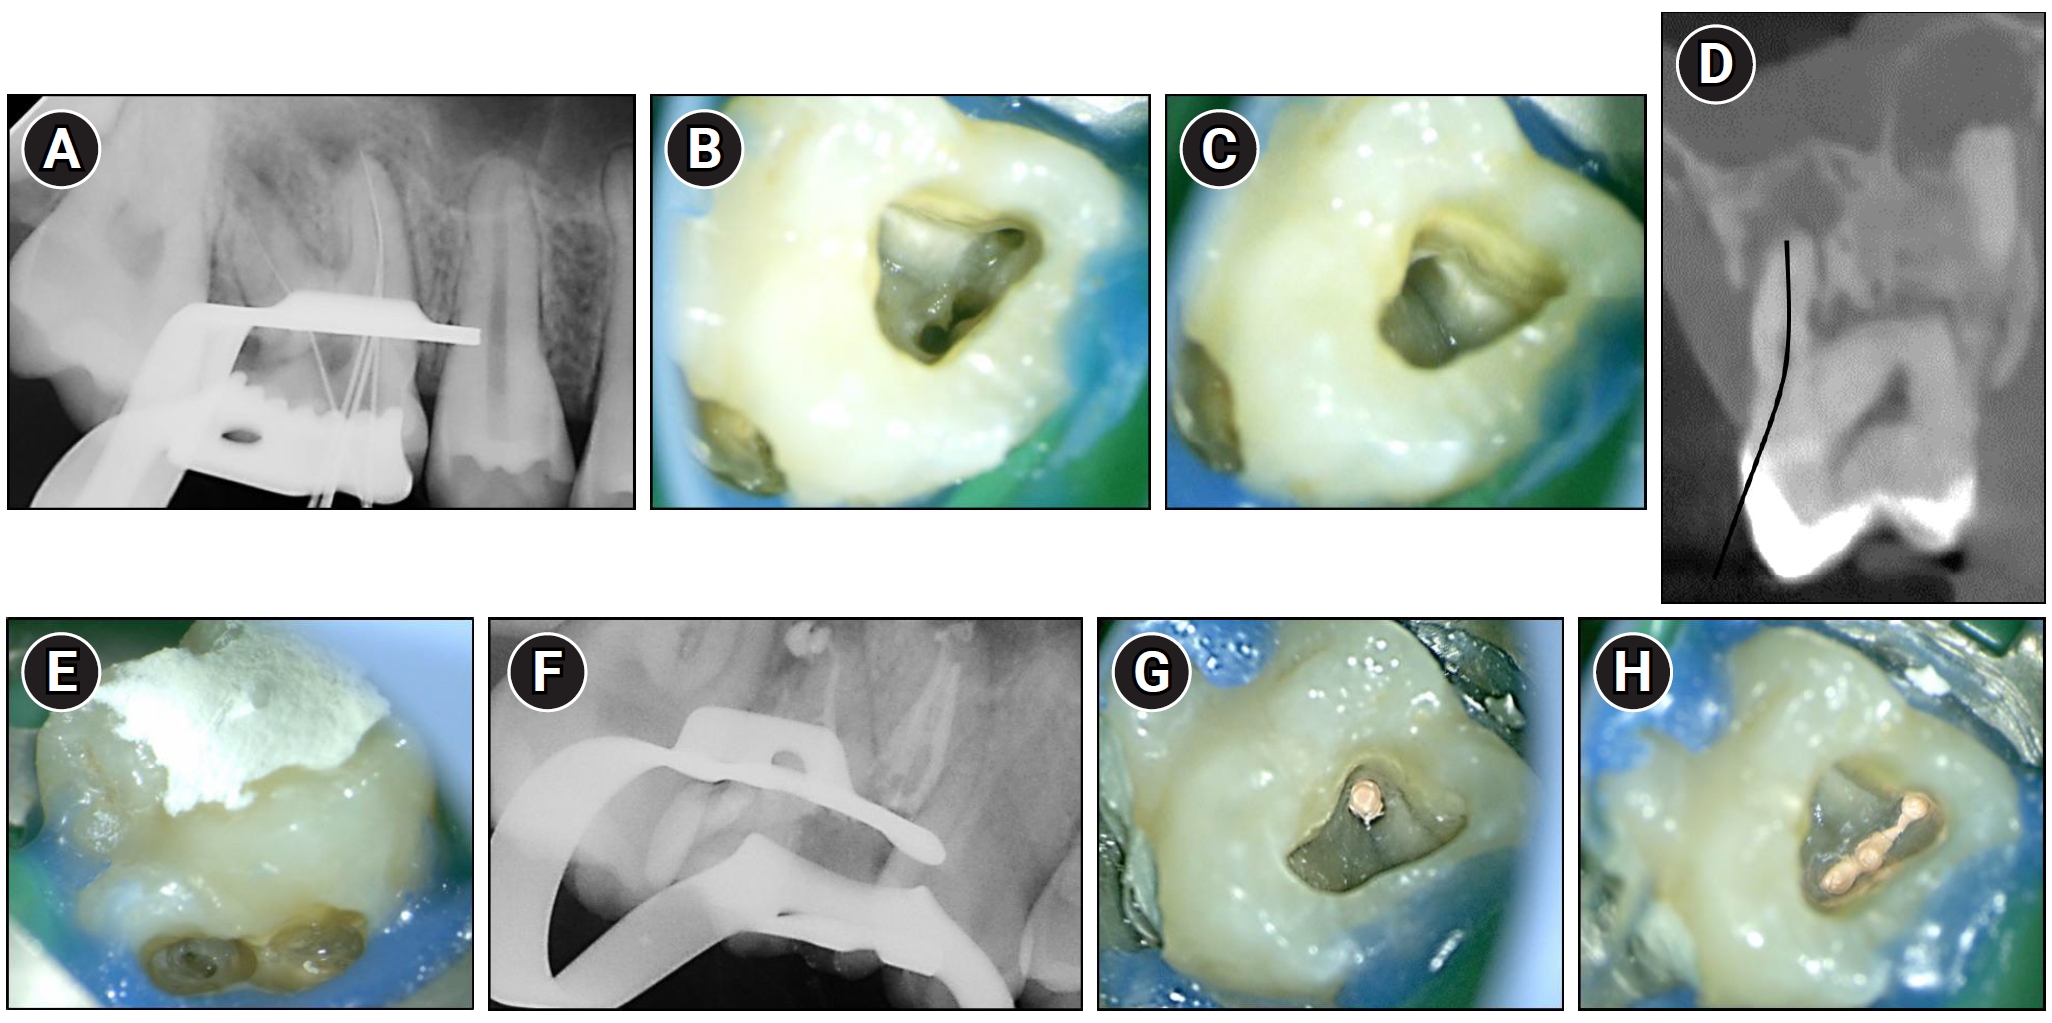

At the first visit, following conventional access cavity preparation, pulp extirpation and working length determination were performed for four buccal canals—three within the mesiobuccal root and one within the distobuccal root (Figure 2A–C). A glide path was established using a HyFlex EDM 10/.05 glide path file (Coltène/Whaledent, Altstätten, Switzerland). Canal shaping was subsequently carried out with a HyFlex EDM 20/.05 taper preparation file, followed by enlargement using a 25/~ HyFlex One File and final finishing using the 40/.04 HyFlex EDM finishing file. Irrigation was performed using 2.5% sodium hypochlorite (NaOCl). For intracanal medication, a calcium hydroxide-based paste (Metapaste Plus; Meta Biomed, Cheongju, Korea) was placed into the canals. The access cavity was temporarily sealed with a temporary restorative material (Caviton; GC Corp., Tokyo, Japan).

Endodontic management of maxillary right first molar (#16). (A) Working length radiograph taken after conventional access cavity preparation, showing four files in the buccal canals. (B, C) Clinical photographs of the pulp chamber floor showing three canal orifices in the mesiobuccal root and one in the distobuccal root. (D) Cone-beam computed tomography sagittal view showing the cervical access route chosen based on presumed palatal canal location. The black curved line indicates the presumed path for cervical access to the palatal canal. (E) Clinical image showing the perforation area after failed palatal canal identification. (F) Post-obturation radiograph confirming canal filling in three mesiobuccal and one distobuccal canal. (G) Clinical image showing obturation of the distobuccal canal with gutta-percha. (H) Clinical image showing well-condensed gutta-percha filling in the mesiobuccal canals.

As the palatal canal was not connected to the main pulp chamber (Figure 1F), a separate access cavity was planned to locate the palatal canal. An attempt was made to access the canal via a cervical approach, which was deemed appropriate given the canal morphology (Figure 2D). However, the palatal canal could not be identified during the procedure, and a perforation occurred (Figure 2E). The perforation site was subsequently repaired using Biodentine (Septodont, Saint-Maur-des-Fossés, France) and resin-modified glass ionomer (Fuji II LC, GC).

At the second visit, intercommunication among the three mesiobuccal canals was confirmed by observing the flow of 2.5% NaOCl during irrigation. After removing the temporary restoration and intracanal medicament, canal patency was reestablished, and the canals were prepared for obturation. Final irrigation was performed using 2.5% NaOCl, followed by passive ultrasonic irrigation (Endosonic Blue 2; Maruchi, Wonju, Korea). Obturation was performed using a sealer-based technique with a calcium silicate sealer (CeraSeal; Meta Biomed). Following master cone fitting in all four buccal canals, root canal obturation was completed (Figure 2F–H).

Interestingly, the palatal canal was found to be anatomically separated from the main pulp chamber, necessitating access through the palatal cervical region (Figure 2D). Such a configuration, in which the palatal canal is anatomically separated from the main pulp chamber, has not been previously reported in the literature. Therefore, the present case highlights a novel anatomical variation associated with MIM that has not been documented in the existing literature.